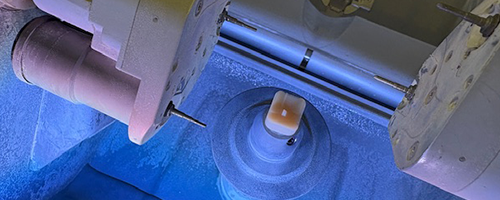

Bei biadent verbinden wir fortschrittliche Behandlungsmethoden mit höchster handwerklicher Präzision. Durch den Einsatz neuster Technologien garantieren wir Ihnen eine diagnostisch fundierte und therapeutisch exzellente Versorgung.